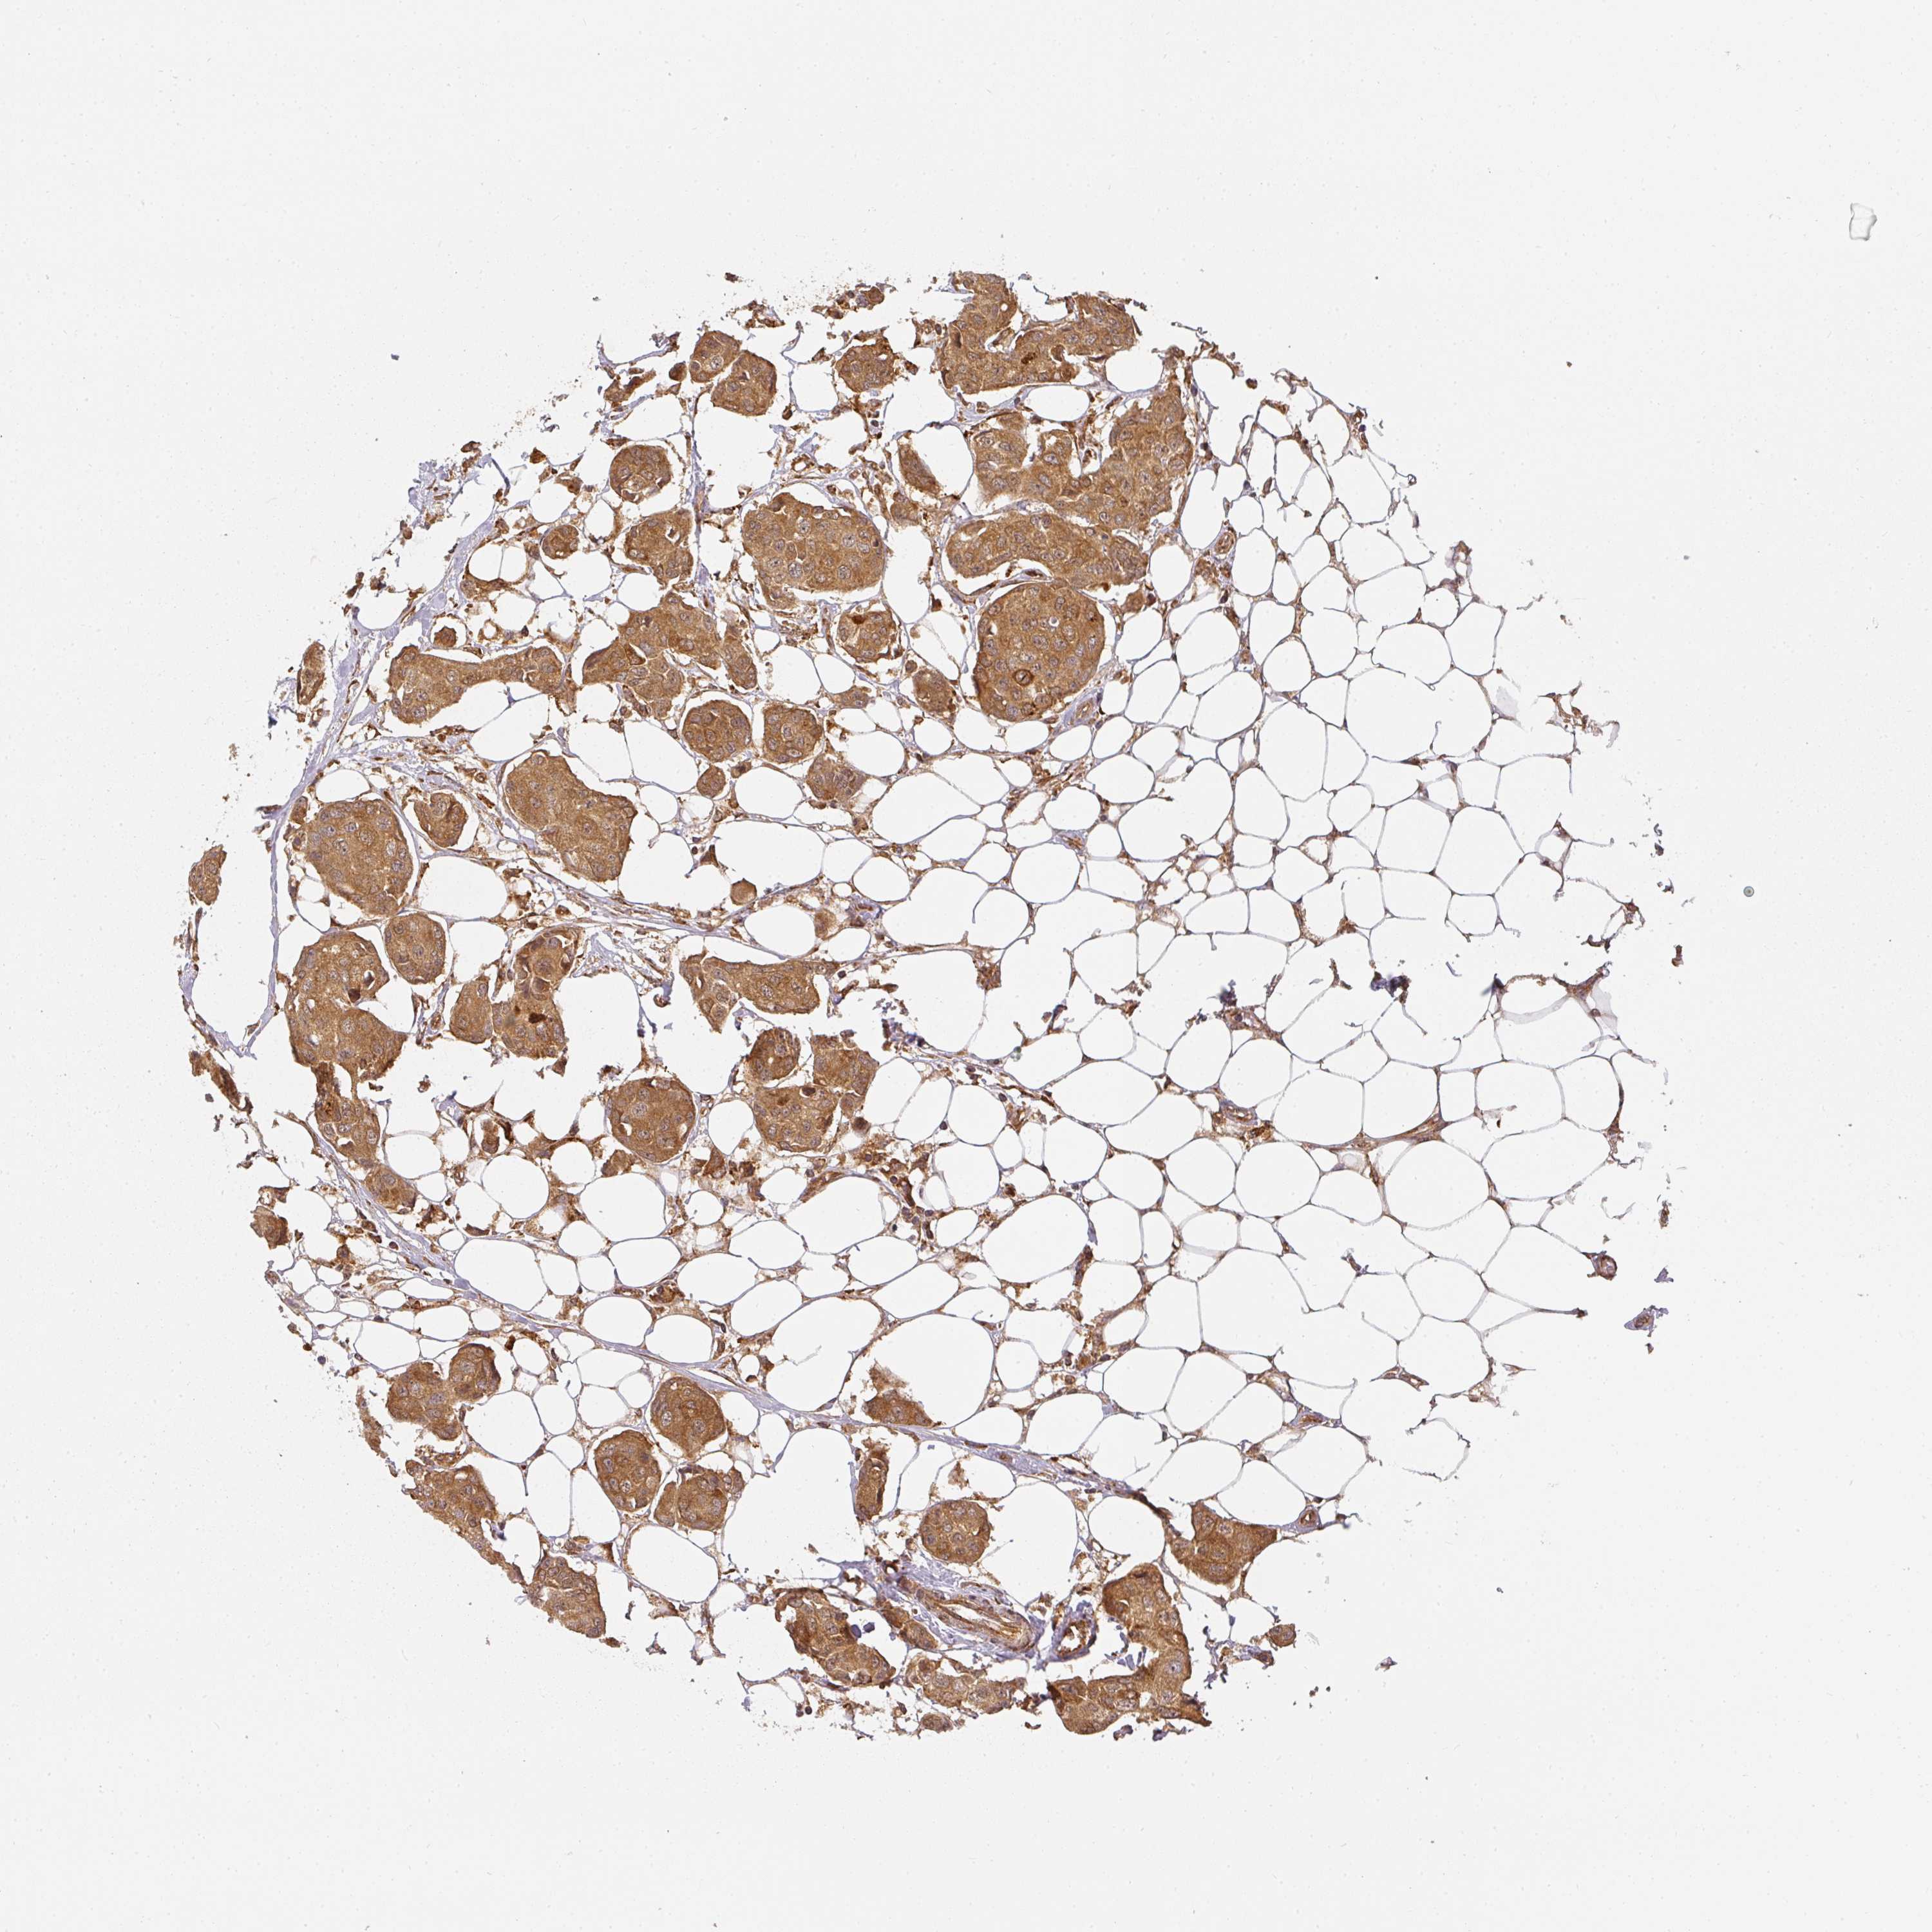

CANCER BREAST CANCER Show tissue menu

BRCA TCGA BRCA VALIDATION PROTEIN EXPRESSION